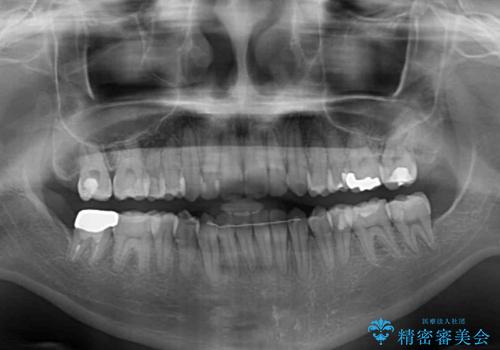

- オープンバイトのため、話しているときの見た目が気になるとのことで来院された患者様です。

下顎骨は左側にシフトしており、咬み合ったときには奥歯と前歯の一部しか接触していない状態でした。

骨格的な左右差は歯列矯正は改善できないため、上下歯列が全体的に接触することをゴールとしてインビザラインにて矯正治療を行うこととしました。

前歯のデコボコの解消と並行して上下の奥歯を圧下させるようにすることで、前歯を接触させるように計画しました。

上下の隙間に舌が入り込むことがオープンバイトの原因であったため、舌の筋肉のトレーニングも並行して行い、後戻りの抑制を図りました。